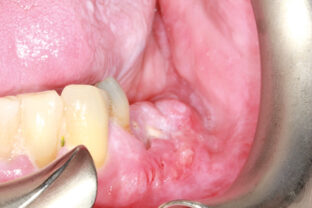

Robertson Fig 6A - Oral Health Group

www.oralhealthgroup.com tissues lesions pathologic oralhealthgroup

Porcelain veneers. Downing dental. Robertson fig 6a